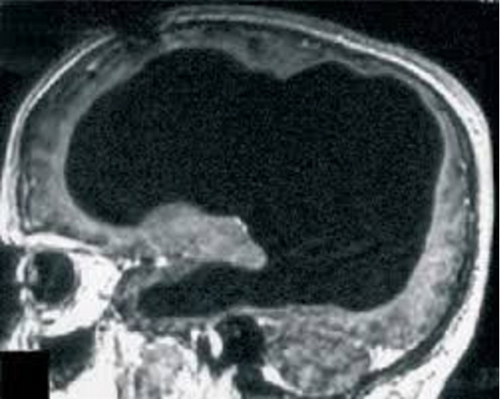

Năm 2014, các bác sĩ ở tỉnh Sơn Đông, Trung Quốc đã bị sốc khi họ phát hiện một người phụ nữ 24 tuổi đã sống mà không có tiểu não – một phần quan trọng của não chứa đến 50% tổng số tế bào thần kinh. Mọi người hầu hết phải dựa vào tiểu não để điều khiển giọng nói, hành động, sự chú ý, ngôn ngữ.

Đặc biệt, người phụ nữ này không hề biết về tình trạng của mình cho đến khi cô đi khám vì có biểu hiện buồn nôn và chóng mặt. Khi ấy, các bác sĩ đã tiến hành chụp cắt lớp và nhận thấy toàn bộ tiểu não của cô không hề có. Phần không gian trống được lấp đầy bởi dịch não tủy. Điều thú vị không chỉ ở việc tiểu não thiếu hụt mà là ở khả năng tự bù đắp kỳ diệu của bộ não.

Các nhà nghiên cứu vẫn không hiểu làm thế nào cô gái này có thể sống ngần ấy năm mà không hề có tiểu não.  Người phụ nữ này chỉ bị ảnh hưởng vận động nhẹ, phát âm hơi lắp bắp. Mẹ cô cho biết cô không thể đứng một mình cho đến khi 4 tuổi và không thể nói câu dễ hiểu cho đến khi lên 6 tuổi. Cô cũng gặp một ít rắc rối trong việc giữ thăng bằng.

Theo các nhà nghiên cứu, đây là điều vô cùng độc đáo và có giá trị nghiên cứu sâu, chứng tỏ bộ não có sức mạnh kỳ diệu hơn chúng ta từng nghĩ.